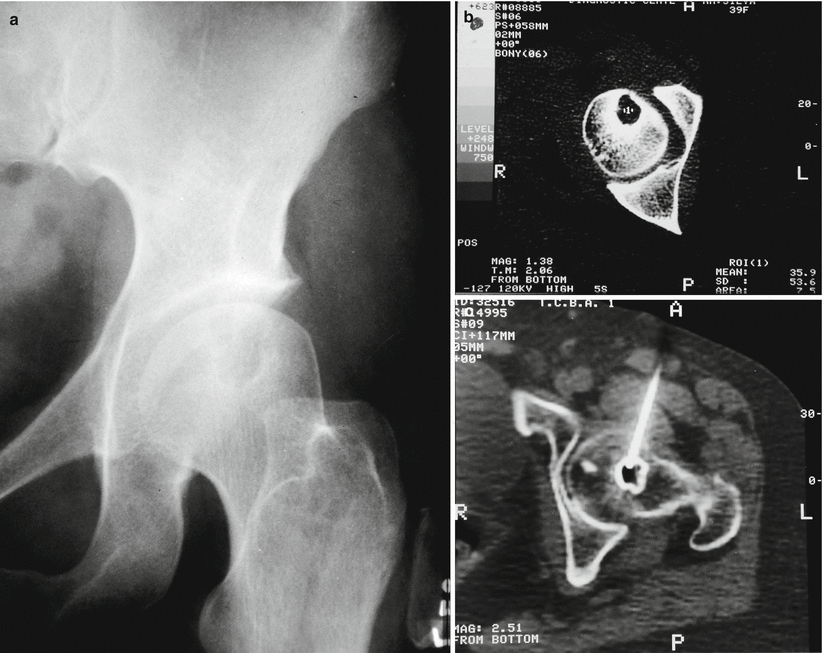

From www.semanticscholar.org

Figure 2 from Management of juxta articular giant cell tumors around What Is Juxta Articular Osteoporosis Ra is the prototype of osteoimmunologic disease where bone loss is one of the most characteristic findings. Ra causes joint swelling, pain, and bone and cartilage destruction leading to functional disability and reduced quality of life. Rheumatoid arthritis (ra) is an autoimmune chronic connective tissue disease that produces persistent systemic inflammation, with joint inflammation. Background juxtaarticular osteoporosis is an early. What Is Juxta Articular Osteoporosis.

From www.researchgate.net

Radiograph of the pelvis including thigh (Anteroposterior view What Is Juxta Articular Osteoporosis Ra causes joint swelling, pain, and bone and cartilage destruction leading to functional disability and reduced quality of life. Rheumatoid arthritis (ra) is an autoimmune chronic connective tissue disease that produces persistent systemic inflammation, with joint inflammation. Background juxtaarticular osteoporosis is an early sign of inflammation in conventional radigraphy in rheumatoid arthritis. Ra is the prototype of osteoimmunologic disease where. What Is Juxta Articular Osteoporosis.